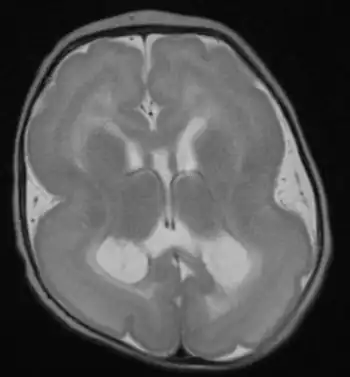

Lissencephalic brain of a human, lacking surface convolutions (Gyrification) | |

Lissencephaly (/ˌlɪs.ɛnˈsɛf.əl.i/, meaning "smooth brain")[1] is a set of rare brain disorders where the whole or parts of the surface of the brain appear smooth.[2] It is caused by defective neuronal migration during the 12th to 24th weeks of gestation resulting in a lack of development of brain folds (gyri) and grooves (sulci).[3] It is a form of cephalic disorder. Terms such as agyria (no gyri) and pachygyria (broad gyri) are used to describe the appearance of the surface of the brain.